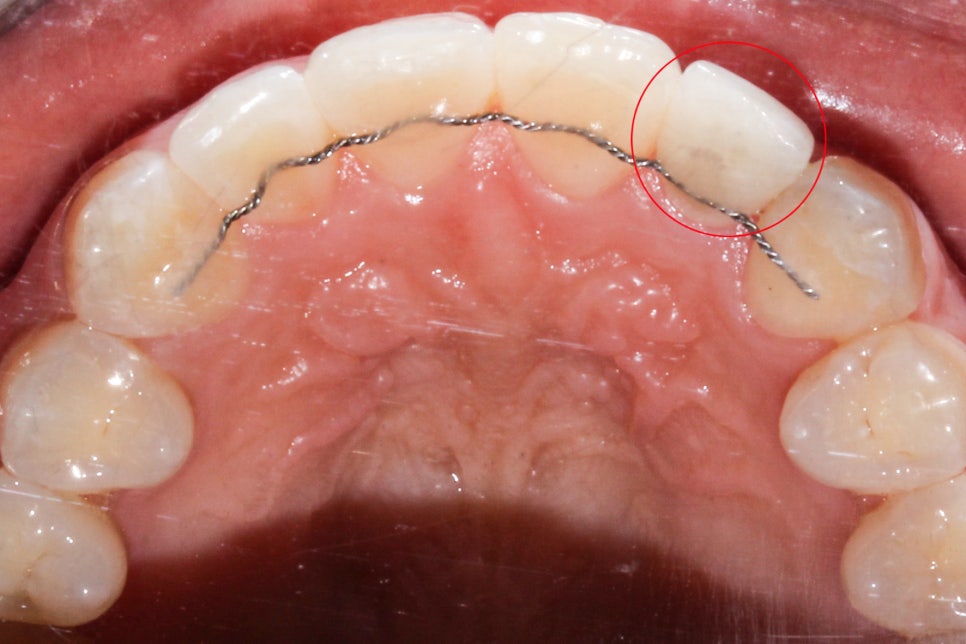

뻐드렁니 교정 전 상악과 하악의 교합면 사진입니다.

상악 교합면을 확인해보면 중절치가 순측으로

뻐드러져 나간 모습을 볼 수 있는데요,

기준치의 역할을 하는 송곳니의 위치가

좋기 때문에 발치 없이 비발치 교정으로

치아를 교정할 수 있을 것으로 예상됩니다.